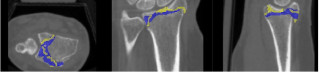

Introduction: Numerous established classification systems for distal radius fractures and the corresponding surgical treatment strategies are based on the subdivision of intra-articular fractures into key fragments, which are separated by fracture lines or comminution zones. However, the morphology of the intervening fracture zones remains poorly understood. The aim of this study was to gain a deeper understanding of fracture zones in intra-articular distal radius fractures and to develop a deep learning-based method for the automated segmentation of these zones using computed tomography (CT) data.

Methods: A dataset comprising 59 manually segmented and annotated CT scans of intra-articular distal radius fractures served as the ground truth. Fracture zones were algorithmically extracted from segmentations of individual bone fragments and were visually validated on a sample basis. A 3D U-Net was then trained to segment fracture zones in new CT scans. Various preprocessing steps, such as data augmentation, region-of-interest (RoI) cropping, and targeted modifications of the fracture zones, were implemented to optimize the model’s accuracy.

Results: The best-performing model achieved a Dice score of 0.2944 and an Intersection over Union (IoU) of 0.1784 for the task of automated fracture zone segmentation. These comparatively low values were attributed to the challenges associated with generating a reliable ground truth dataset.

Discussion: Fracture zones are often extremely difficult to delineate in CT scans, even for clinical experts, and frequently require interpolation based on professional experience during annotation. This contributes to a degree of uncertainty in the training data. Furthermore, the course of fracture zones follows a structural logic that is only partially discernible in CT imaging. Even fractures classified as identical can exhibit significantly different fracture zone morphologies.